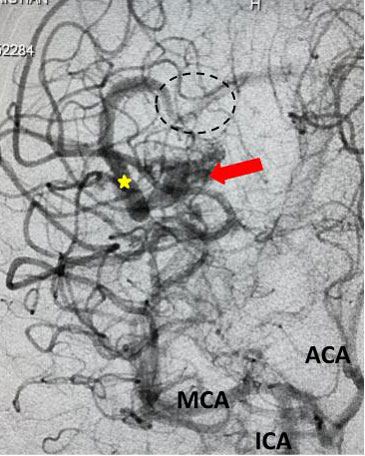

Fig 5. Comparison, pre (5A) and post-embolization (5B) AP view, late-arterial phase of a right internal carotid artery (ICA) injection. On the right, near total obliteration of the AVM (red arrow). Draining vein (yellow star), residual veins (blue stars).

The student underwent NBCA-embolization of the AVM via the dominant feeding posterior cerebral artery with care to avoid embolizing the calcarine branches and avoid NBCA penetration into the single draining vein (Fig 4 and 5). Following the intervention, a tiny feeder from the middle cerebral artery remained (Fig 4).

Fig 2. AP view, mid-arterial phase of a right internal carotid artery (ICA) injection. The large tortuous draining vein (yellow star) with the suggestion of clot (dotted circle) can be seen. AVM nidus (red arrow), MCA (middle cerebral artery, ACA (anterior cerebral artery).